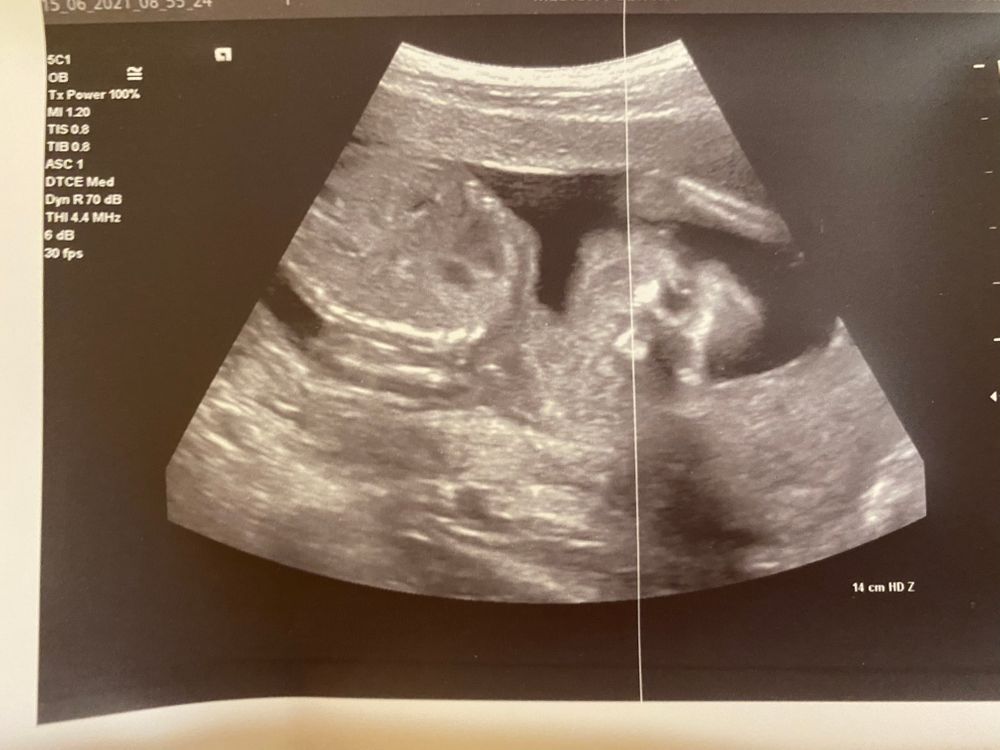

Узи в 16 недель .И предлежание плаценты

О предлежании на данном сроке не говорят. Не информативно. А узиста лучше сменить, если вы "изменяете" больничному. Фотка супер!!!